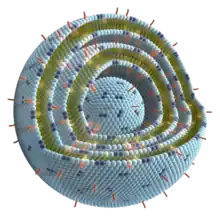

In the investigational therapeutic cancer vaccine (formerly known as Stimuvax, L-BLP25, BLP25 liposomal vaccine or BLP25 liposome vaccine), the antigen tecemotide is anchored — together with the adjuvant 3-O-deacyl-4′-monophosphoryl lipid A (MPL) — in the membrane of the liposome made from the lipids cholesterol, dimyristoyl phosphatidylglycerol (DMPG), and dipalmitoyl phosphatidylcholine. MPL is a derivative of the lipid A molecule found in the membrane of Gram-negative bacteria used as an adjuvant to initiate a non-specific immune stimulus, thereby stimulating the activation of antigen-presenting cells (APCs) through the toll-like receptor 4 (TLR-4) as well as macrophages. MPL is also used as an adjuvant in other vaccines, like Cervarix, a vaccine against certain types of cancer-causing human papillomavirus (HPV).[1]

The precise mixture of lipids in the vaccine, as well as providing the structure of the liposome, is also formulated to enhance the uptake of the vaccine by the aforementioned antigen-presenting cells.[7]